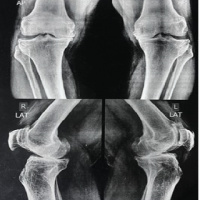

A 28-year-old woman arrived with a 20-year history of gradually increasing pain, swelling, and deformity of the left hemibody, particularly the lower limb, accompanied by functional scoliosis with right-side convexity. Symptoms first appeared in childhood. Upon examination, notable hypertrophy and joint stiffness were observed in the left lower limb (Fig. 1), with a 4.5 cm length discrepancy in the left lower limb, left-sided genu valgum, foot varus, and equinus deformity, along with hyperpigmentation and a scar over the left ankle. The skin over the lumbar region exhibited hyperpigmentation with a 4.5 cm soft tissue swelling at the L3 level (Fig. 2) and nodular thickening over the medial malleolus. Hip and knee fixed flexion deformities measured 25° and 90°, respectively. Digital radiographs and computed tomography (CT) scans demonstrated diffuse cortical thickening and hyperostosis affecting the pelvis, femur, tibia, talus, calcaneus, and tarsal bones of the left side, with partial joint fusion and medullary cavity obliteration, characteristic of “candle wax dripping” [4] (Fig. 3-7).